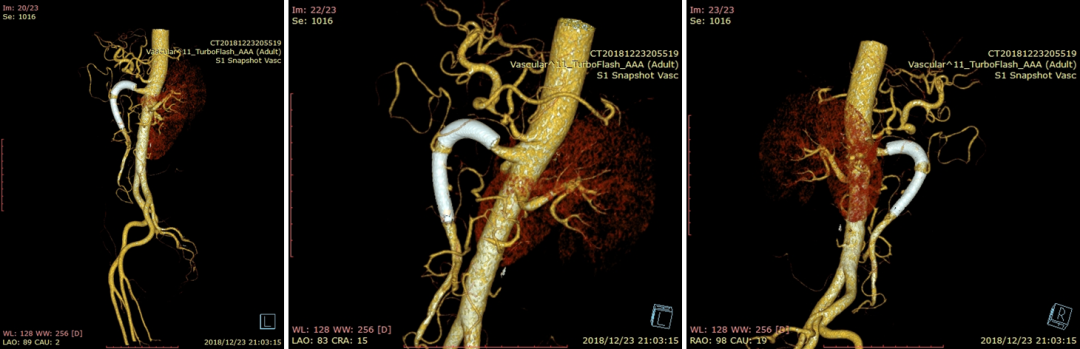

20181223CTA(术后6天)

20230530CTA(术后1周):夹层动脉瘤隔绝完全

20230913CTA(术后14周):血肿吸收完全